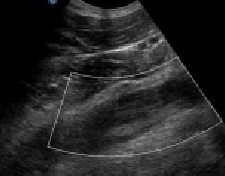

Zachary Obinna Enumah, MA; Jeffrey M. Chinsky, MD, PhD

A 16-year-old boy presented to the emergency department after being referred by his primary care physician for having failed outpatient therapy for pneumonia.